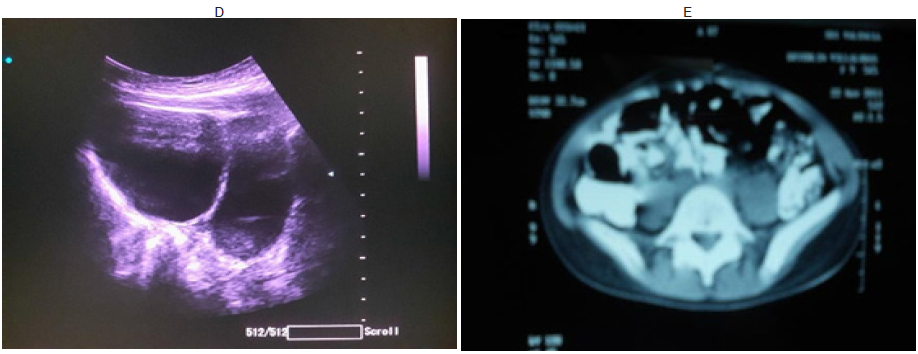

Adicionalmente se realizó ecografía pélvica, previa plenificaciòn vesical que reveló útero, desplazado a la derecha, de forma piriforme, bordes regulares y miometrio homogéneo de 49 x 39 x 43 mm en sus dimensiones, con un endometrio lineal de 2 mm. Ovario derecho de eco patrón micro folicular de 15 x 21 x 31 mm. Volumen: 5,10 mL. Ovario izquierdo: de eco patrón quístico ocupado por imagen heterogénea bilobulada con componente quístico predominante de 38 x 28 x 39 mm y un volumen de 65 cc, con efecto doppler negativo; concluyéndose el diagnostico de imagen compleja (ecomixta) para uterina izquierda. (Fig. 2 D, E).

Se realizó TAC helicoidal de abdomen y pelvis con doble contraste (oral y endovenoso) con progresión milimétrica desde las bases pulmonares hasta la sínfisis púbica, reportándose: bases pulmonares sin infiltrados ni consolidaciones: hígado, bazo, páncreas y glándulas suprarrenales con densidad adecuada, riñones de morfología, tamaño, ubicación y densidad conservadas. Cámara gástrica distendida por contraste oral el cual progresa adecuadamente en asas delgadas y marco colónico, vejiga plenificada. En pelvis se evidencia útero lateralizado a la derecha de morfología y tamaño conservados. En el margen izquierdo del área retro-uterina se identifica imagen de LOE predominantemente hipodensa con coeficiente de atenuación en rango líquido con alto contenido proteico y de pared gruesa hipodensa bien definida, cuyos diámetros son 59 x 41 mm en sentido transversal y anteroposterior respectivamente. Anexos no evaluables. Buena definición de la grasa peri rectal, peri vesical y de fosas isquiorectales sin evidencias de adenopatías en cadenas linfáticas regionales. Esqueleto regional sin lesiones aparentes. Se concluye: LOE quístico complejo en margen izquierdo del área retro-uterina. Glándulas suprarrenales sin aparentes anormalidades (ver Fig.2.)